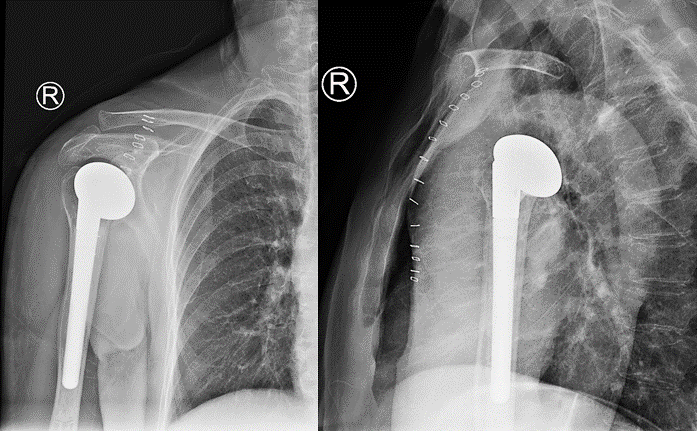

术前CT显示右肱骨近端粉碎性骨折、移位明显

术后X线片显示人工肱骨头假体位置满意